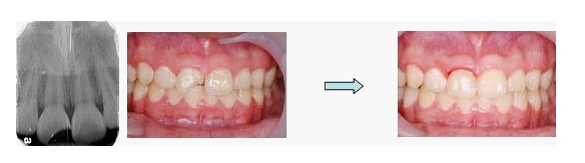

兒童牙科 (被架拐子了 - 牙冠斷裂)

青少年小朋友常常打籃球撞傷或騎腳踏車不慎跌倒,首當其衝是門牙斷裂。家長常會驚惶失措,小朋友也會嚇到六神無主。

牙齒斷裂常有多種分類,在此不詳述。

處理原則為二大方向:

1. 如傷及牙髓神經,則應儘快保護牙髓或是直接根管治療(醫師 會依症狀判斷)

2. 是否牙齒需要固定,如需要固定時大致為輕輕力量的固定,時間約1~2週。通常牙周韌帶會癒合完全。但仍需定期觀察。